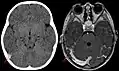

Синус-тромбоз при нативной компьютерной томографии (сагиттальная реконструкция)

Синус-тромбоз при нативной компьютерной томографии (слева) и МРТ в режиме T1 с контрастным усилением (справа)